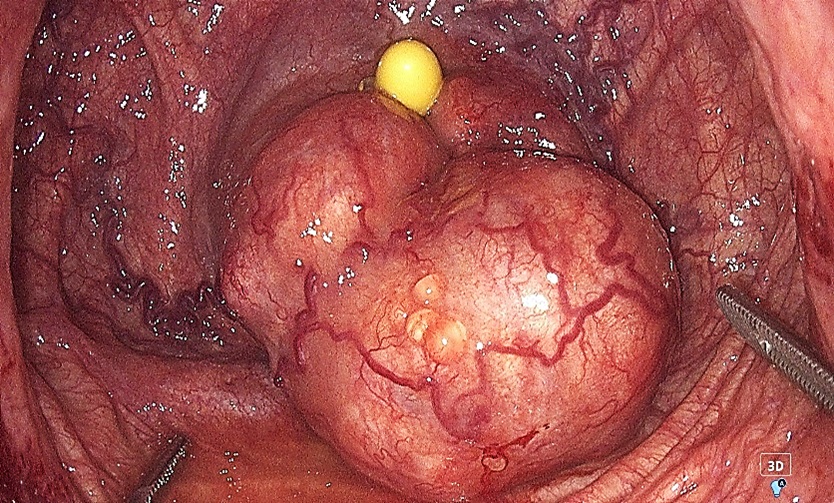

Введение. Лапароскопическая аденомэктомия является методом выбора в лечении гиперплазии предстательной железы (ГПЖ) крупных и гигантских размеров. Данный метод отличается эффективной коррекцией инфравезикальной обструкции, низкой частотой геморрагических осложнений и инконтиненции, уменьшением сроков послеоперационного восстановления, а также повышением качества жизни пациентов.

Материалы и методы. В основу данного ретроспективного исследования включены результаты лечения 36 пациентов, которым была выполнена лапароскопическая трансвезикальная аденомэктомия по поводу ГПЖ. Критерии включения пациентов в исследование: объём предстательной железы свыше 80 см3; показатель максимальной скорости потока мочи ниже 15 мл/с; отсутствие инфекции нижних мочевых путей, нейрогенных расстройств мочеиспускания и трансуретральных оперативных вмешательств в анамнезе. Всем исследуемым пациентам выполняли цистометрию (наполнения и опорожнения) непосредственно до операции и через 3 – 6 месяцев после.

Результаты. Средний возраст больных составил 65,8 ± 4,21 года. Средний объём предстательной железы был равен 148,5 ± 17,9 см3, среднее значение суммарного балла симптоматики заболевания по шкале IPSS перед началом лечения — 19,4 ± 2,3 балла. Максимальная скорость потока мочи колебалась от 3,2 до 11,3 мл/с и в среднем составила 6,2 ± 1,6 мл/с. В раннем послеоперационном периоде ни у одного из исследуемых пациентов не отмечено осложнений тяжелее I степени по классификации Clavien-Dindo. После операции было отмечено статистически значимое снижение показателя детрузорного давления с 20,29 (± 2,9) до 11,24 (± 2,9) см вод. ст., а также увеличение максимальной скорости потока мочи с 6,24 (± 1,61) до 25,1 (± 5,05) мл/с.